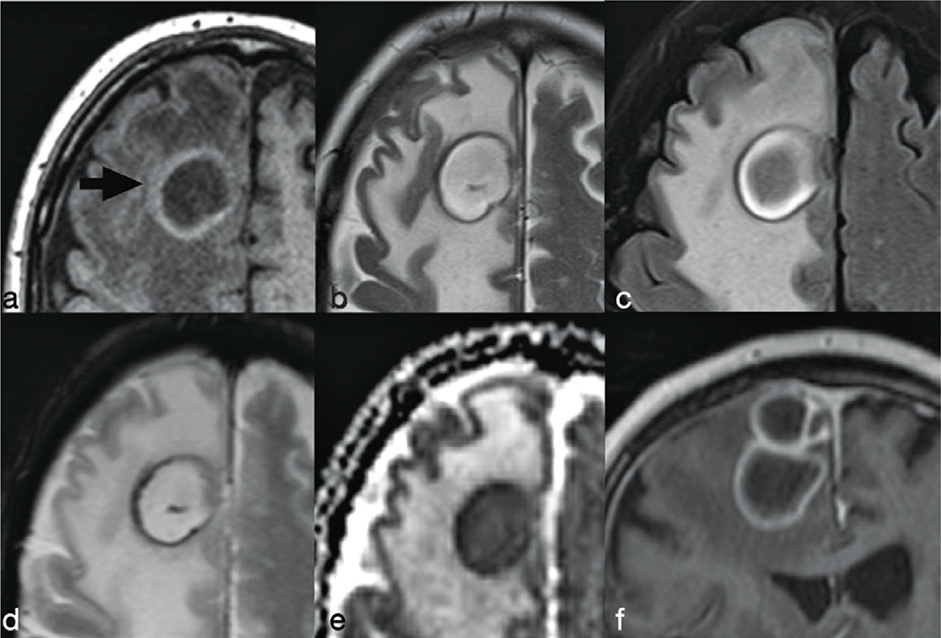

The abscess capsule is well-defined, smooth and complete. It shows a layered aspect, hypointense on FLAIR/T2-wi and hyperintense on T1-wi. The presence of collagen fibres and macrophages releasing free radicals are considered responsible for the short T1 and T2 of the rim due to their paramagnetic effect (Figure 2).7 The external low-signal rims on T2-wi could be useful to distinguish abscess from glioblastomas: in this case the rims, irregular or incomplete in the majority of cases, result from the store of haemorrhagic products surrounding the outer layer of the necrotic core.8

FIG 2. Nocardia Abscess in a 64-Year-Old Immunocompromised Man Presenting with Headache. A round lesion with thick capsule hyperintense on T1w (a) and hypointense on T2w/FLAIR-T2w (b–c) is shown. The lesion is characterised by a core of restricted diffusion (d–e). Typical ring-enhancement is present after intra-venous Gd administration; the coronal scan also reveals the presence of multiple lesions (f). A discreet amount of perilesional vasogenic oedema is present too (a–e).

On FLAIR/T2-wi, the abscess is usually surrounded by vasogenic oedema. Moreover, FLAIR images can be useful to help improve the diagnosis of a subarachnoid rupture of the BA with subsequent meningitis (Figure 3). Satellite abscesses that give a polylobate appearance to the BA can occur (Figure 4).